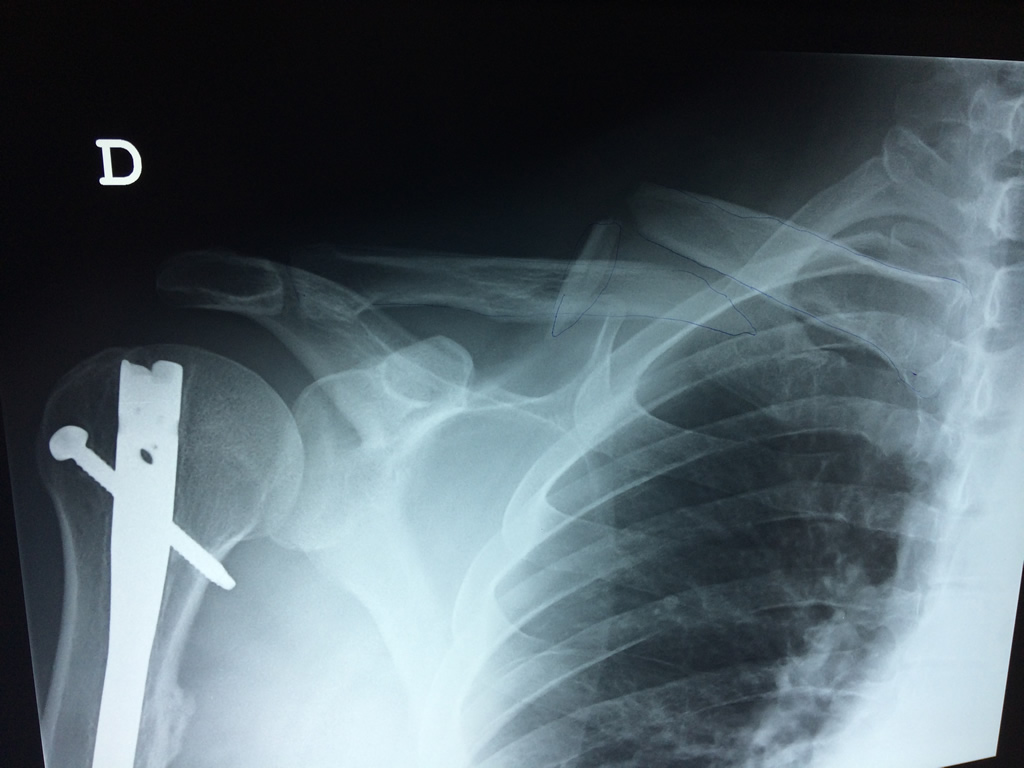

Fémur - Clavícula

La clavícula es un hueso largo, con forma de "S" itálica, situado en la parte anterosuperior del tórax. Junto con la escápula forman la cintura escapular. Se puede palpar por toda su longitud y se extiende del esternón al acromion de la escápula, siguiendo una dirección oblicua lateral y posterior.